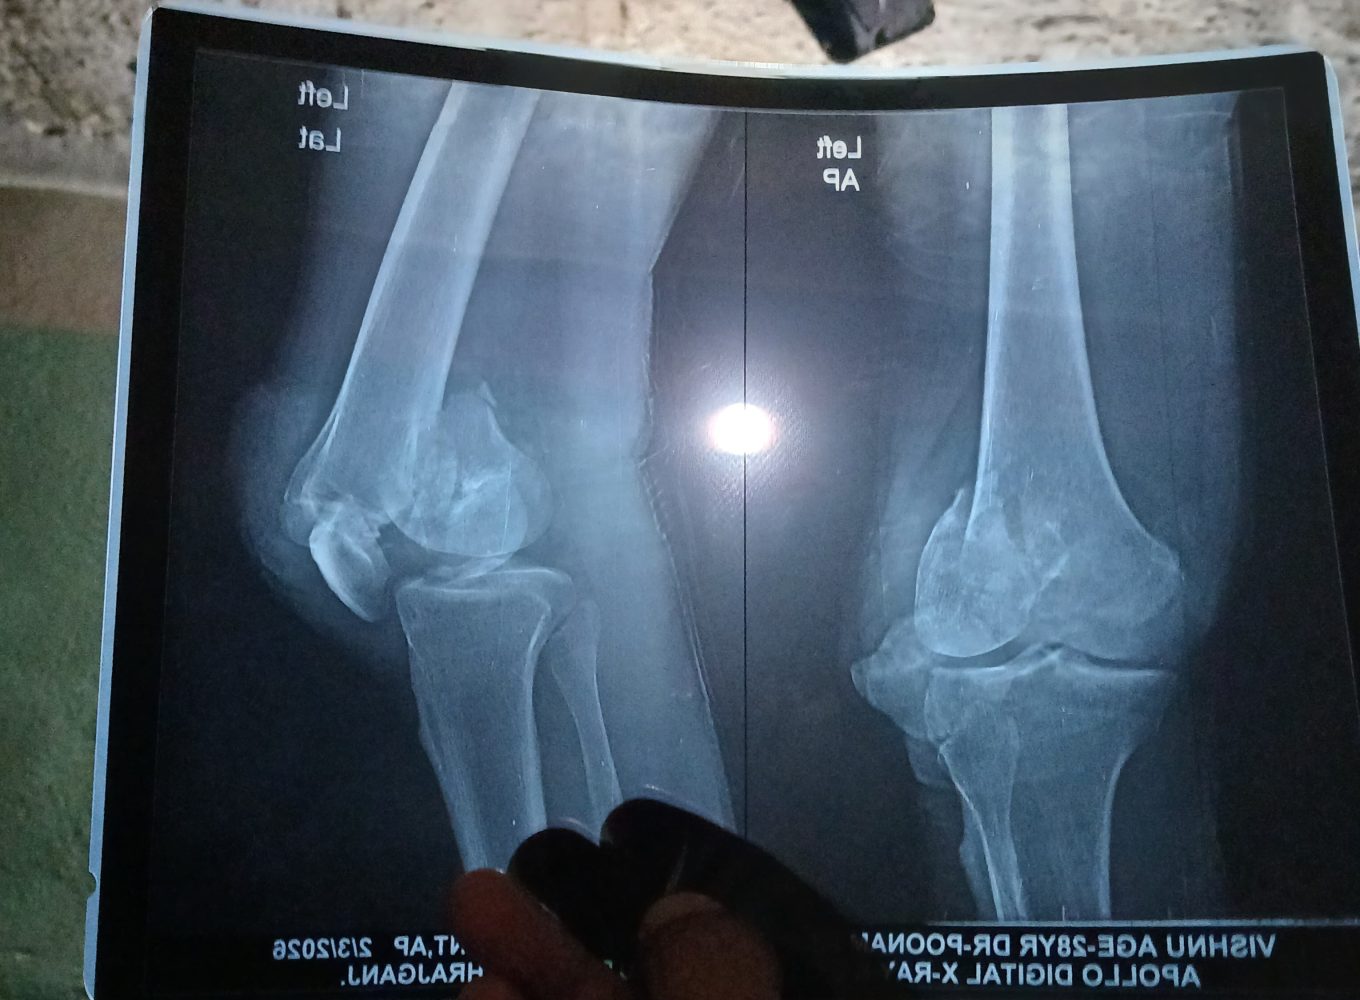

रुपन्देहीको ओमसतिया गाउँपालिका–३ दुमदुमवा निवासी विष्णु अर्याल दुर्घटनामा परि खुट्टामा गम्भीर चोट लागेकोले स्वास्थ्य समस्याबाट पीडित भई उपचाररत रहनुभएको छ।